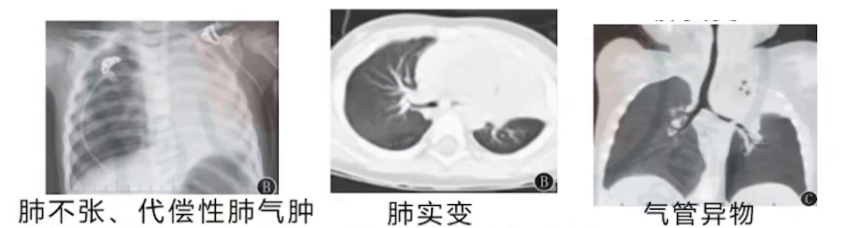

影像学检查(肺不张、代偿性肺气肿、肺实变,甚至直接发现气管异物征象),支气管镜直接发现或患儿自行咳出支气管塑型物质可确诊。

(2)影像线索:肺实变区域密度均匀、支气管充气征大部分消失,是高度提示塑型支气管炎的典型表现。